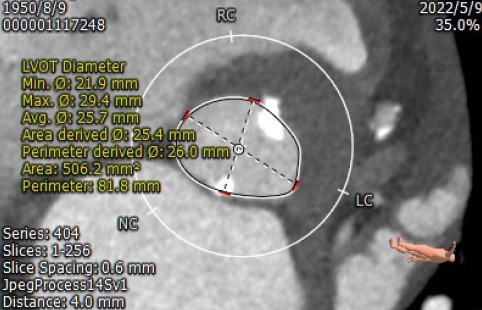

主动脉根部CT测量

瓣环周长72.9mm

平均径23.0mm

LVOT周长81.8mm

平均径25.7mm

左冠高度:11.7mm

右冠高度:14.2mm